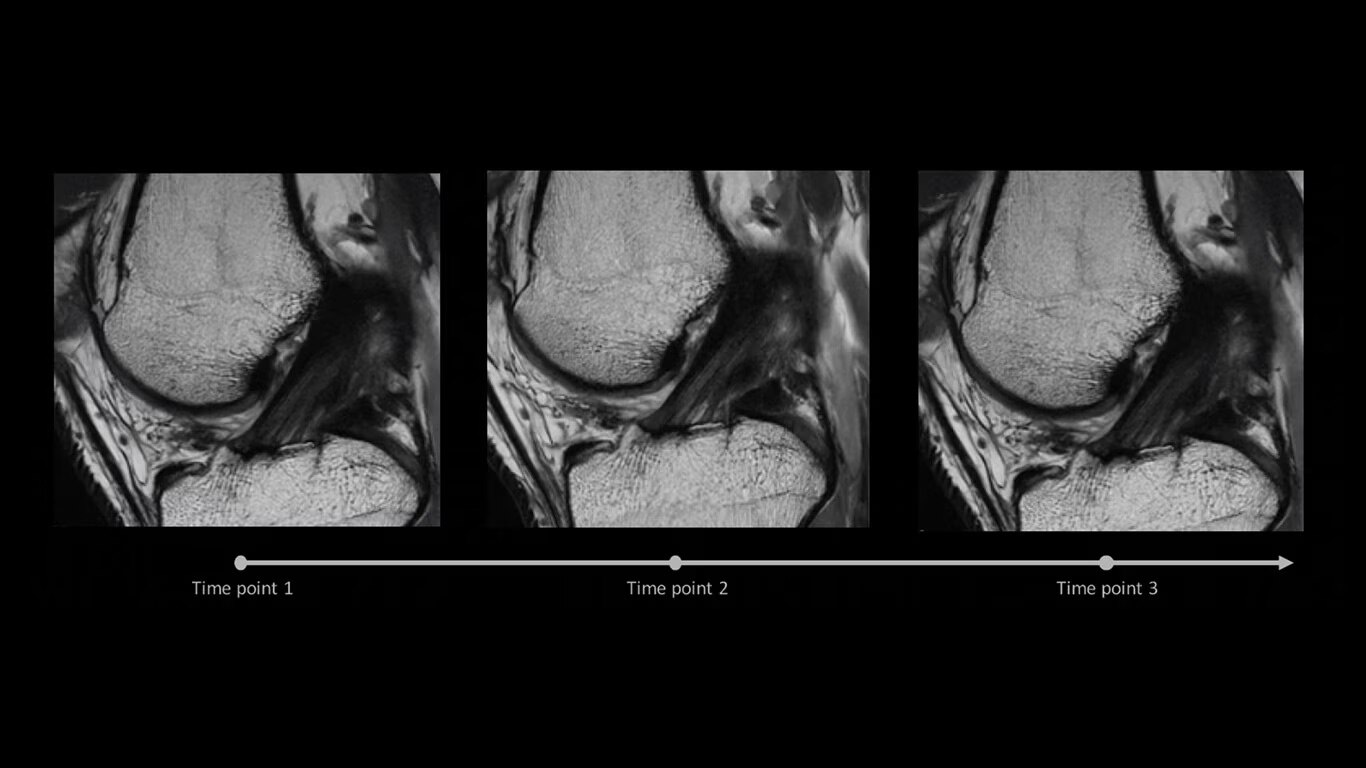

AIR x™ automatically detects patient anatomy and prescribes MRI slices

Eliminate the sources of variation by letting processes flow. AIR x™ uses deep-learning algorithms created from a database of 10's of thousands of images to automatically detect patient anatomy and prescribe MRI slices for routine and challenging neurological and knee exams, delivering consistent and quantifiable results. The automated workflow creates efficiency and reproduces steps used in planning to ensure exam consistency for same patient follow-up.

Automated MRI slice placement

Determine the best MRI slice placement

AIR x™ automatically detects patient anatomy and prescribes MRI slices for routine and challenging neurological and knee exams, delivering consistent and quantifiable results.

Consistent and accurate images

Deliver consistent results

Deliver consistent MRI slice placements across multiple clinical time points, with a deep-learning algorithm that provides efficiency and time savings.